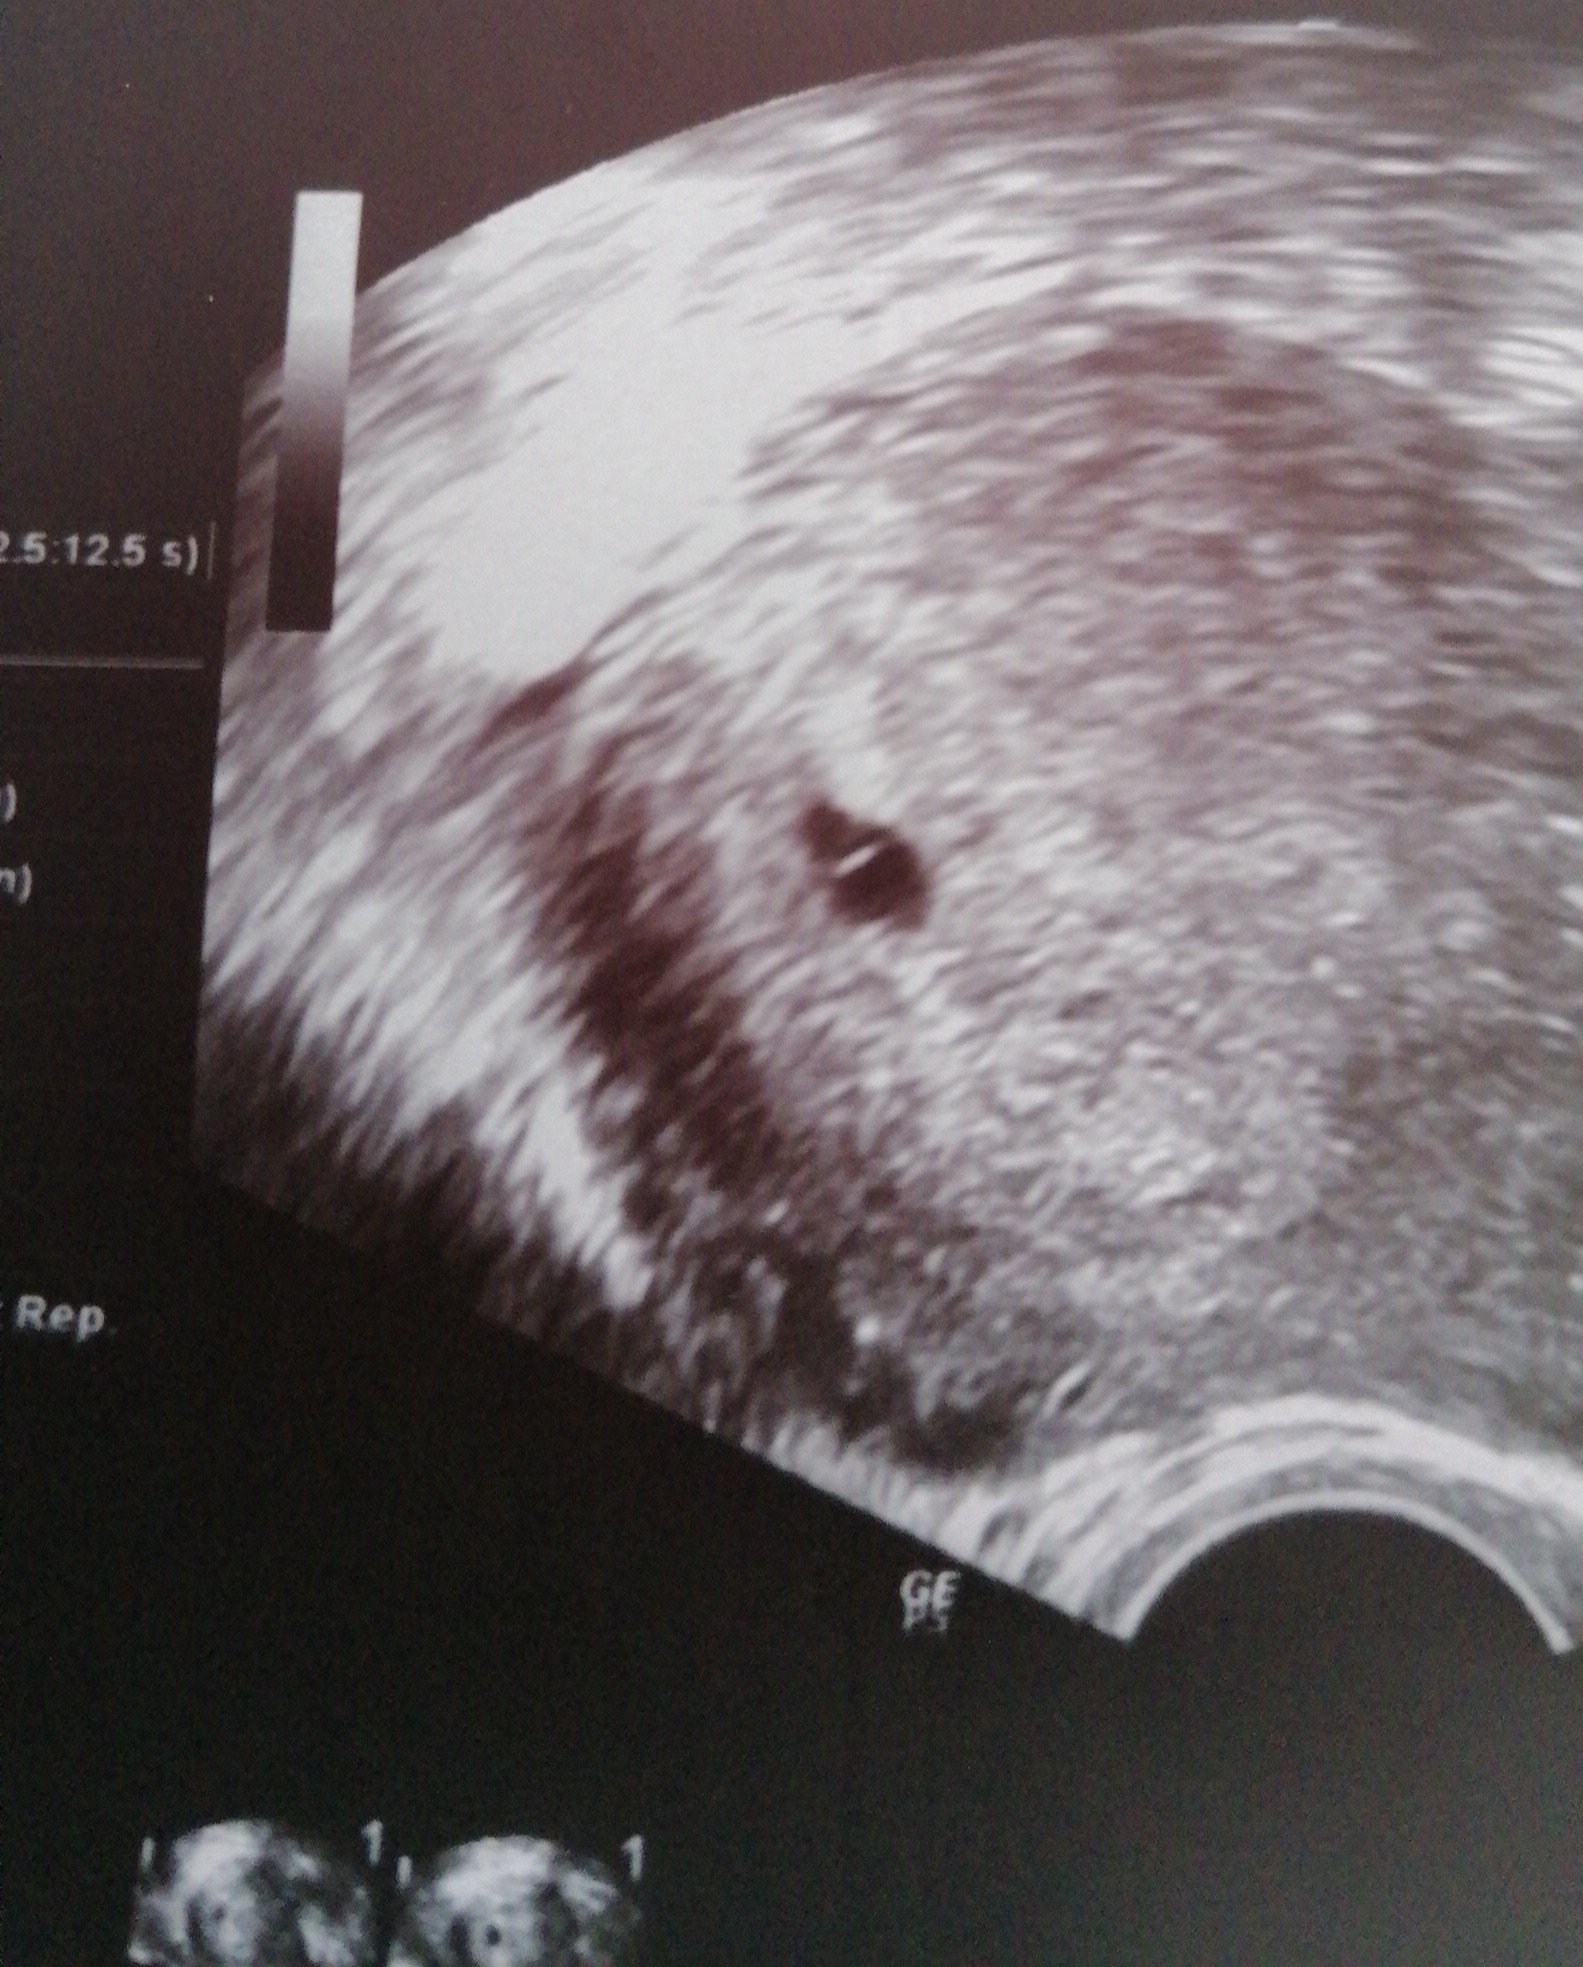

Hejka, ja dzisiaj byłam na wizycie która miałaś umówiona nie będąc jeszcze w ciąży wiec skorzystałam, bo chciałam mieć pewność na tym etapie, ze ciąża jest umiejscowiona w macicy - ciąża jest na prawdę młoda bo według moich obliczeń 4+4 i Pani doktor tez mówiła ze bardzo wczesna około 4-5 tygodnia, czy w tym czasie któraś z Was była i tez był maleńki pęcherzyk ? Czy któraś widziała już coś więcej? Wiadomo jak pewnie każda z nas, analizuje, doszukuje się i zamartwiam lekko 🤭

Ja mam podobne zdj 😊 u mnie jest młodsza ciąża niż apki pokazują. Także nie stresuj się 😊

• IMG_20220427_185455.jpg

IMG_20220427_185455.jpg

489,2 KB · Wyświetleń: 82